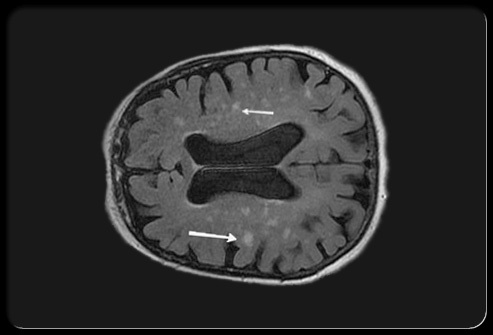

How is vascular dementia diagnosed?

Neurological signs and vascular disease on imaging